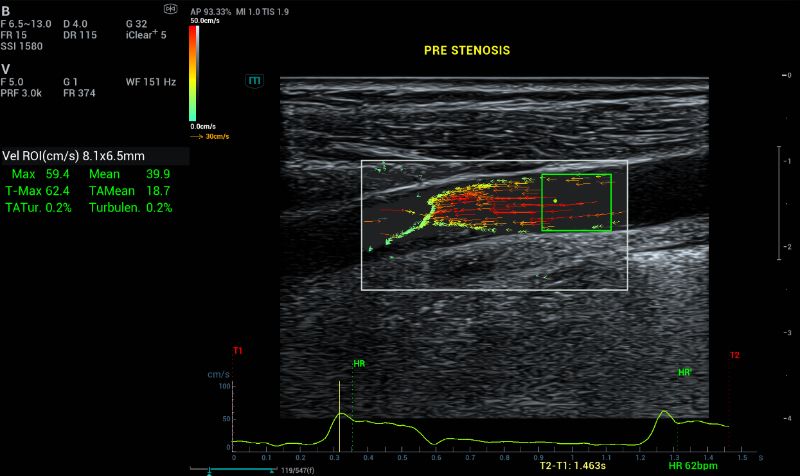

A novel ultrasound-based technology called V Flow demonstrated the dynamic of the blood flow. The fluidity will be displayed with arrows indicating the flow process. Both the magnitude and direction of the flow can be measured at any location in the vessel. V Flow-detected hemodynamic parameters were related to plaque components and plaque vulnerability. V Flow has the potential to be an effective tool for investigating patients with severe carotid plaque.

The V Flow dynamic imaging shows that the length of the vector arrows at site of the carotid stenosis was longer than the surrounding vessel wall. The color of vector arrows at the carotid stenosis site was orange or red with faster flow velocity. However, the most common vector arrows at the distal and proximal sites of the stenosis were slower green or yellow vector arrow (Fig 7).

Unlike B-mode and color Doppler US, V Flow is independent of the ultrasound angle; therefore, V Flow uses a high frame rate to track high speeds in real time and to intercept transient flow phenomena resulting in a high space–time resolution.

Reverse & turbulence flow are demonstrated by the arrow going towards different directions. Higher velocity are seen with red and longer arrow at the stenosis site.

Fig.7: Reverse & turbulence flow are demonstrated by the arrow going towards different directions. Higher velocity are seen with red and longer arrow at the stenosis site.:

ROI box was placed at the stenosis to measure the Tur. The quantitative instantaneous velocity values is calculated based on the movement of the RBC through the transmission and reception of plane waves.

Fig.9: ROI box was placed at the stenosis to measure the Tur. The quantitative instantaneous velocity values is calculated based on the movement of the RBC through the transmission and reception of plane waves.